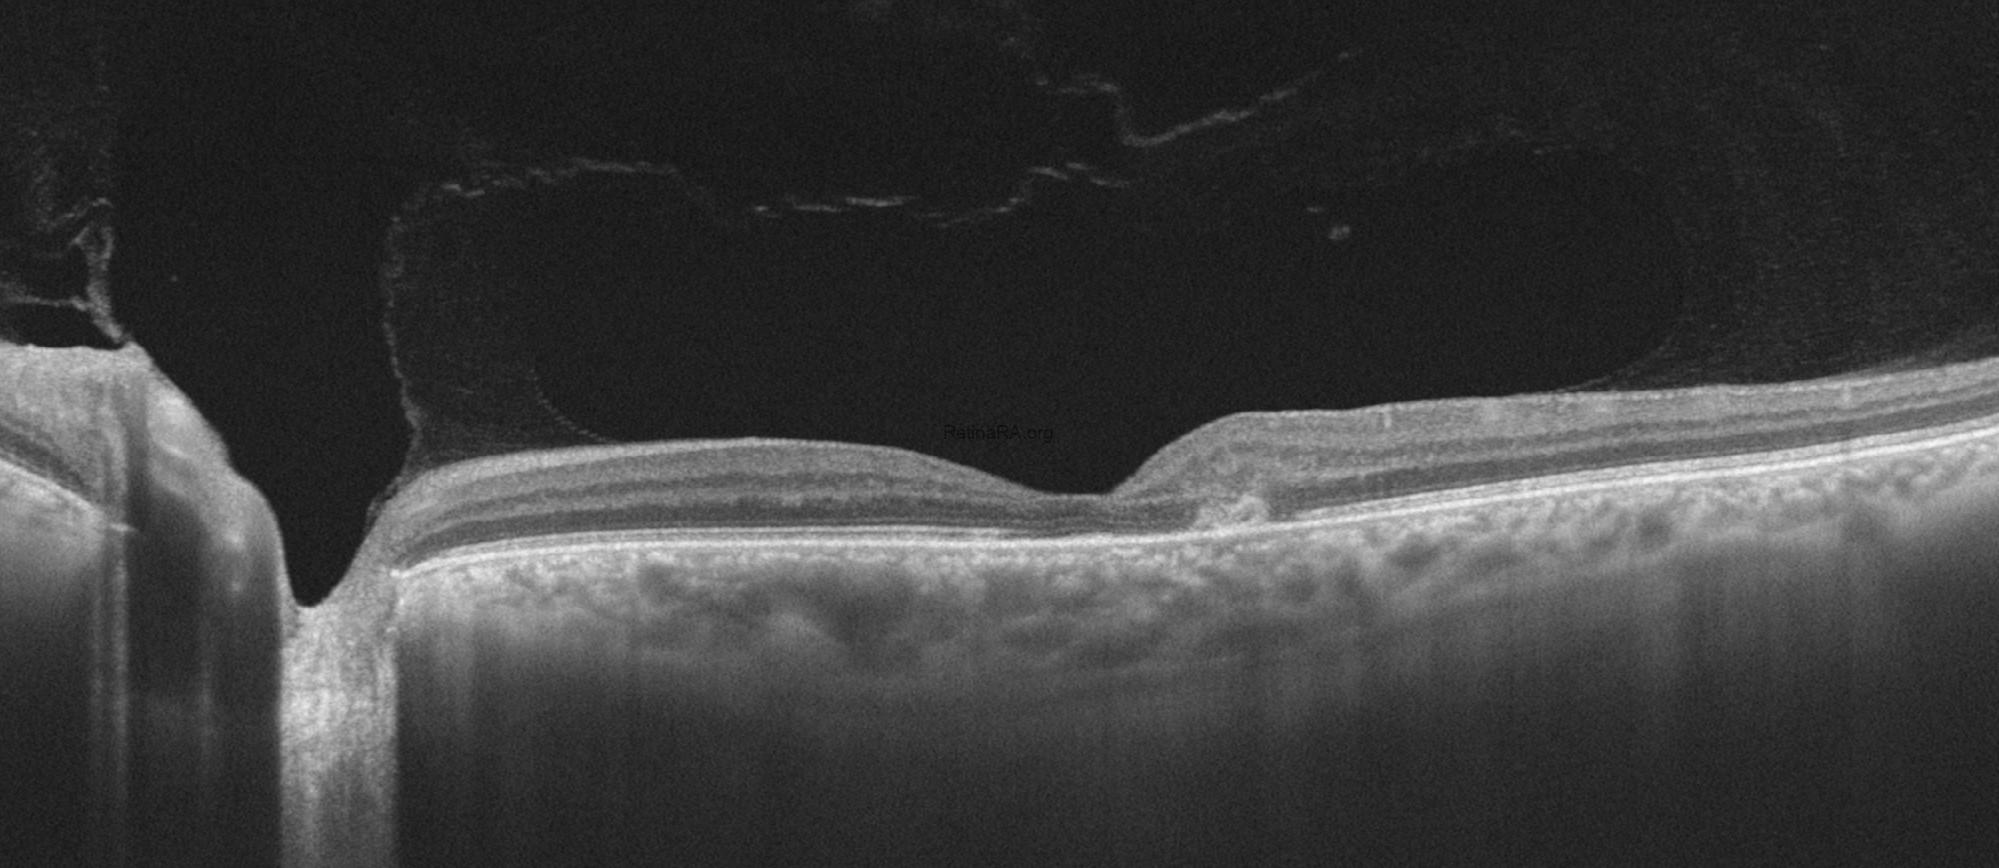

Optical coherence tomography (OCT) demonstrated characteristic parafoveal structural alterations, choroidal neovascularization in both eyes, and Henle fiber layer hemorrhage in the left eye. Early findings include inner and outer retinal cavitations, particularly involving the inner nuclear and outer plexiform layers, often without significant retinal thickening. Disruption and attenuation of the ellipsoid zone are observed in the temporal parafoveal region, reflecting photoreceptor damage. Thinning of the neurosensory retina and loss of normal foveal contour become evident. In the neovascular stage, OCT reveals subretinal hyperreflective material consistent with choroidal neovascularization, frequently accompanied by subretinal fluid, intraretinal cystic changes, and focal retinal thickening.

The patient’s imaging findings after three doses of anti-VEGF therapy are shown below. Visual acuity impoves after treatment to 0.5/0.4.Crystalline deposits are more prominent on color photography of the right eye after anti-VEGF treatment.

After the patient is treated with anti-VEGF injection, disorganization or intraretinal fluid and subretinal exudative fluid findings are resolved and the patient’s acuity returns to baseline.